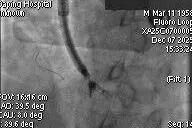

After general anesthesia, the patient underwent jugular vein puncture to establish access. An 18Fr delivery sheath was advanced over a super-stiff guidewire to the mid-to-lower right atrium. Under ultrasound guidance, the delivery system was introduced. A 14T K-Clip® and a 16T K-Clip® device were implanted at the postero-septal commissure annulus and the antero-posterior commissure annulus, respectively. The angle between the device and the annular plane was adjusted through controlled flexion and rotation to orient the device tip toward the target site. Using ultrasound MPR mode, the anchor component was advanced into the annulus. After traction confirmed stability, the clip arms were opened and apposed to the annulus. The anchor component was then retracted to close the clip arms, achieving annuloplasty. The effect was evaluated as satisfactory, and the clip components were deployed.

Delivery system entering RA via SVC

Advancing anchor component under MPR view